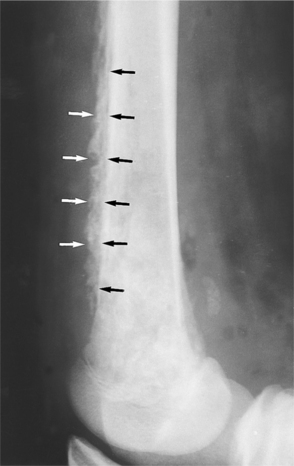

Radiographs may not detect bony abnormality in infections of less than 10 days’ duration. Lytic lesions may be demonstrable on radiographs within 2 weeks of onset of the disease. A periosteal reaction develops later (Fig. 25-3). Magnetic resonance imaging (MRI) and isotope bone scans are the procedures of choice in delineating the disease’s anatomic extent.100 Imaging tests are often used to localize or confirm the presence of infection. MRI is sensitive and provides valuable detail of septic arthritis, spinal osteomyelitis, and diabetic foot infections.77 Radionuclide bone scan can detect early stage disease and is helpful in detection and identifying multiple sites of involvement.17 This procedure may be used as an alternative when MRI cannot be performed or as an adjunct diagnostic tool in people with an uncertain diagnosis.

Figure 25-3 Chronic osteomyelitis. A lateral view of the knee shows the periosteal reaction (arrows) suggestive of chronic osteomyelitis. The bone of the distal femur has a mottled appearance as a result of the infection. (From Mettler FA: Essentials of radiology, ed 2, Philadelphia, 2005, W.B. Saunders.)